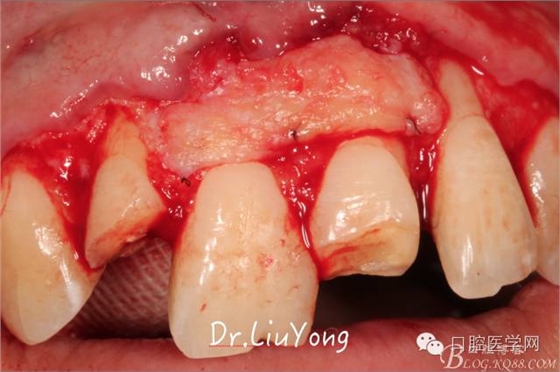

系帶手術(shù)后兩周,進(jìn)行上頜前牙唇側(cè)的牙齦退縮的手術(shù)治療,由于局部附著齦缺如及牙齦厚度不足,因此同期進(jìn)行上皮下結(jié)締組織移植,解決附著齦及牙齦厚度不足的問(wèn)題。

術(shù)中,可見(jiàn)明顯的唇側(cè)骨開裂,如上圖: